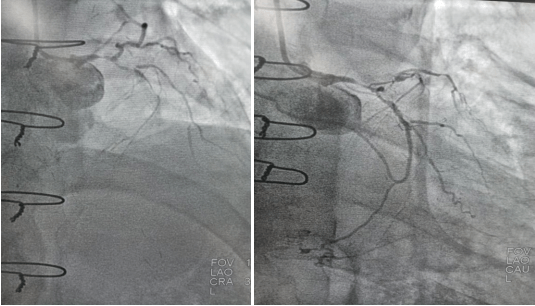

心血管病院吴栋梁院长、CCU李新国副主任、心血管内科二病区赵娟副主任、王端乐主治医师、宋睿主治医师介入团队造影后认真研究患者的病情和影像资料,决定开通闭塞长达11年的右冠状动脉,精确选择器械,选择同轴性及支撑力均好的指引导管,术中选用微导管辅助,软、硬导丝结合等技术,聚精会神、挥汗如雨,终于历经3小时的努力,成功前向开通右冠状动脉,精准选择由远及近“铺设”通过性较好、长度合适的支架 。

(术前术后对比)

术后症状明显改善,活动后无胸闷、胸痛,明显提高患者生活质量,提高患者生存率,使患者绝地逢生。